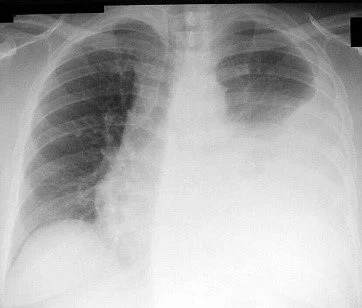

A pneumothorax is a collapsed lung and occurs when air leaks into the space between the lung and chest wall. Tension Pneumothorax is especially deadly.

Tension pneumothorax is a life-threatening condition that can develop when either the visceral pleura is disrupted, or with injury to the tracheobronchial tree. Rapid, accurate diagnosis and appropriate therapy are required to prevent significant atelectasis, hypoxia, circulatory arrest, and possible patient death.